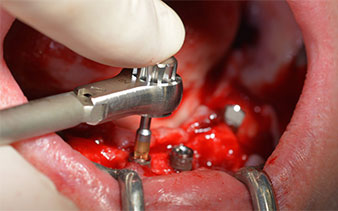

Angled abutments (35°) were screwed in to compensate for the divergence of the distal implants, with the result that the emergence profile of all implants was as perpendicular as possible to the bite plane. This is a prerequisite for occlusal placement of the provisional and subsequently the permanent denture (Fig. 15 and 16).

The impression and bite registration were then performed so that the dental technician could begin producing the provisional restoration immediately. This was then screwed in on the same day (Fig. 17 and 18).